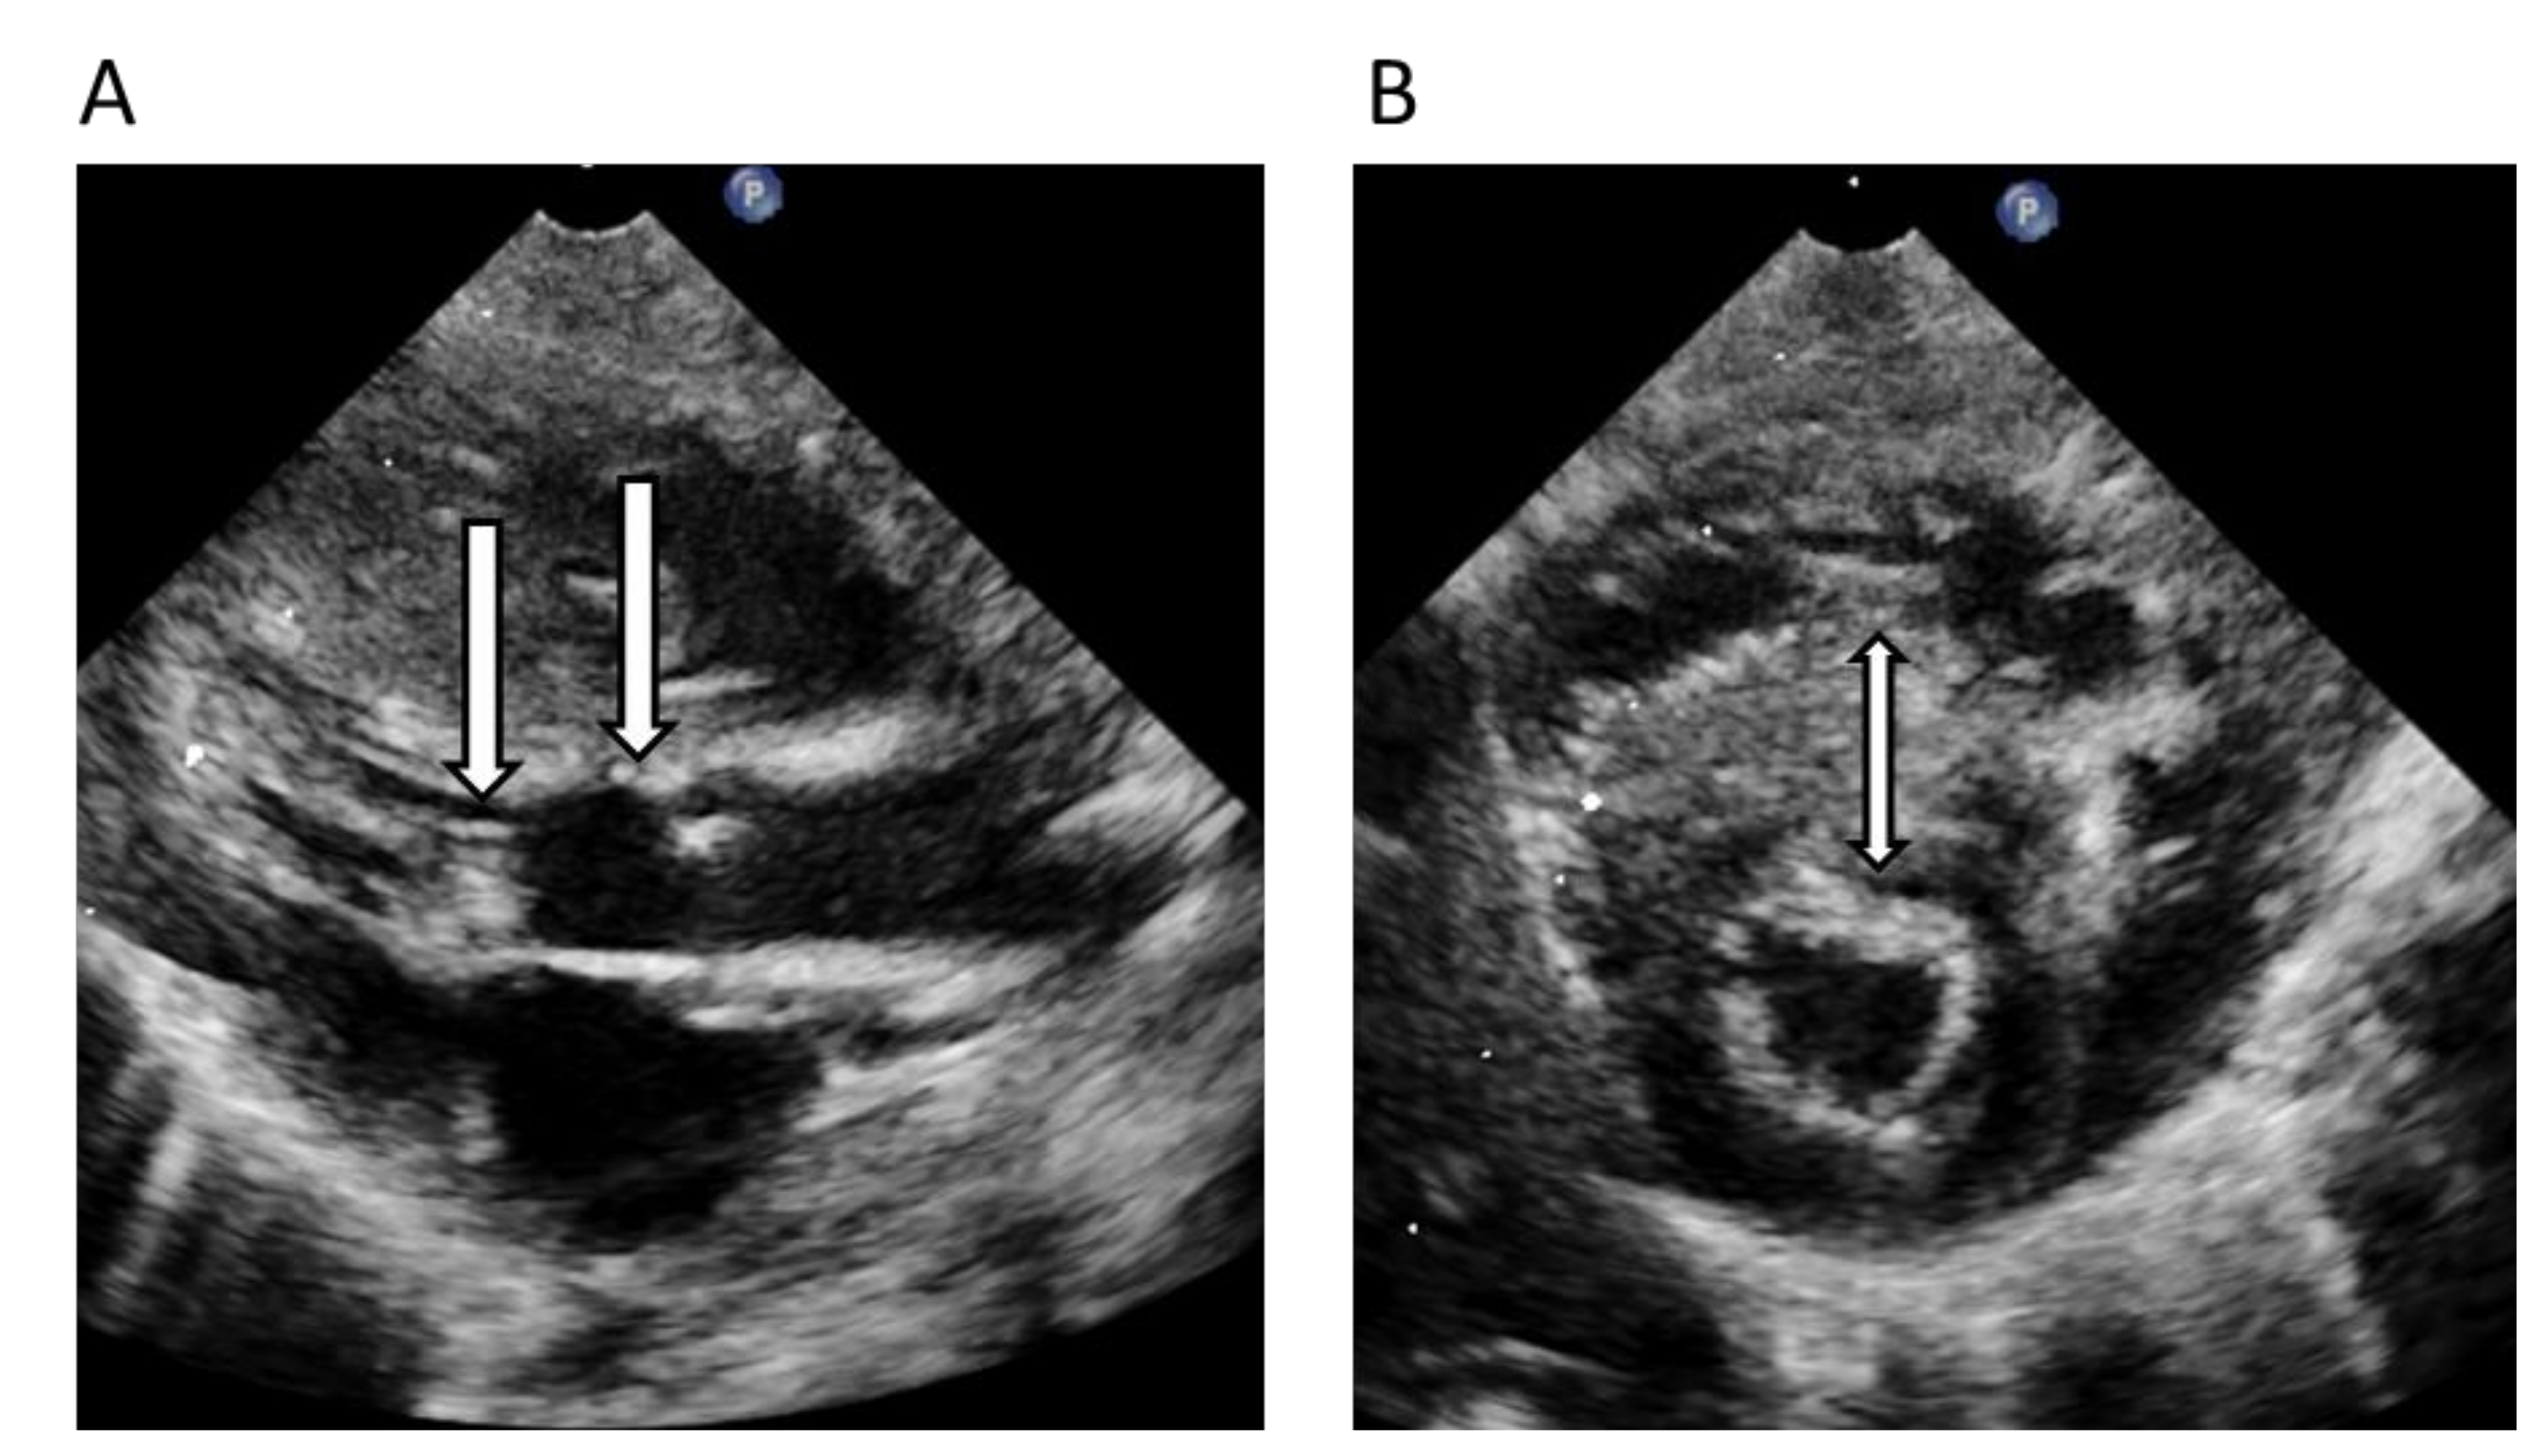

| 6. | II:6 | 11 | F | 2 | HCM/RCM | 3 | 13 | Index patient and brother with SCD as first symptom | PGM1 Chr1(GRCh37):g.64100506G>A, NM_002633.2:c.689G>A, p.G230E | PM2 + PP3 + PS3 Pathogenic/Yes |

| 5. | II:1 | 0.1 | M | 0 | Severe LVOTO infant heart surgery | 2 | 3 | Father with pediatric onset of HCM | MYBPC3 Chr11(GRCh37):g.47359334C>T, NM_000256.3:c.2320G>A, p.A774T | None VUS/Yes |